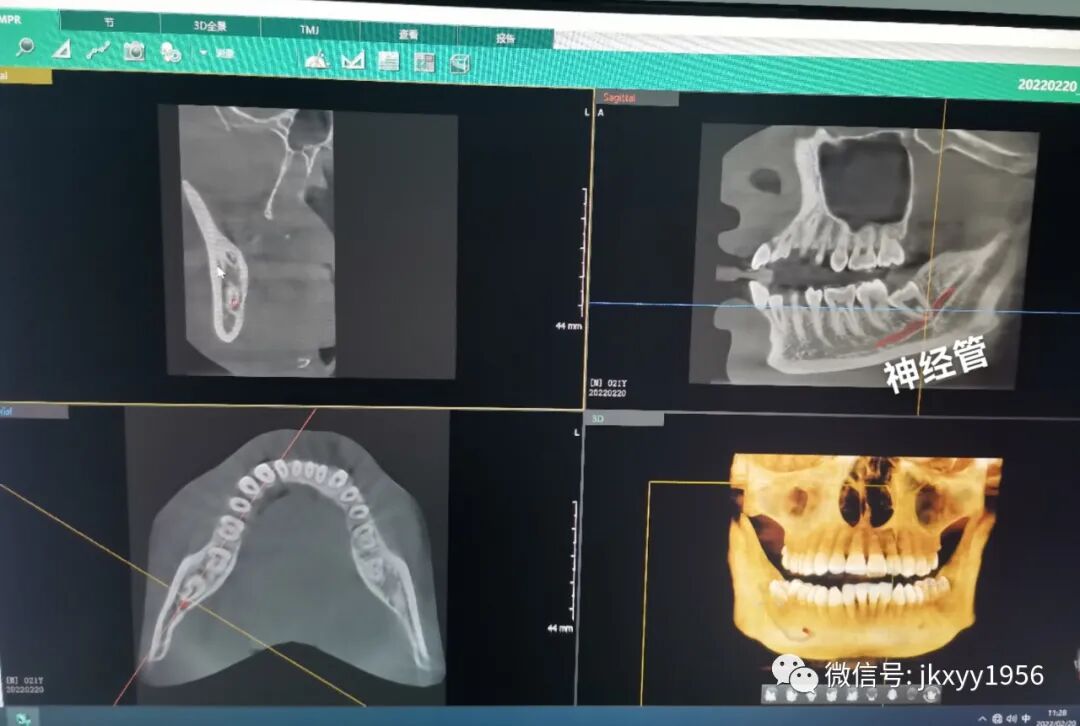

CBCT是目前国际最先进的口腔科专用CT,在业界被誉为神奇的"慧眼",具有扫描快、范围大、精度高、应用广、放射剂量极低的特点。可以通过其强大的处理软件功能以及面部匹配技术迅速形成清晰逼真的三维图像,在智齿拔除、牙种植测量、多生牙定位、颞下颌关节疾病、颌骨三维重建、根管治疗评估、正畸设计等方面提供精准的诊断与治疗依据。

清晰的立体成像